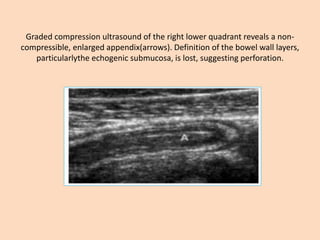

Graded compression ultrasound of the right lower quadrant reveals a non-

compressible, enlarged appendix(arrows). Definition of the bowel wall layers,

particularlythe echogenic submucosa, is lost, suggesting perforation.